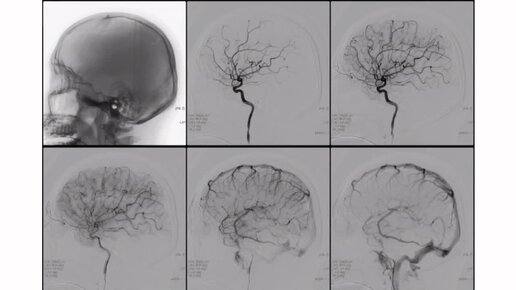

Сосуды